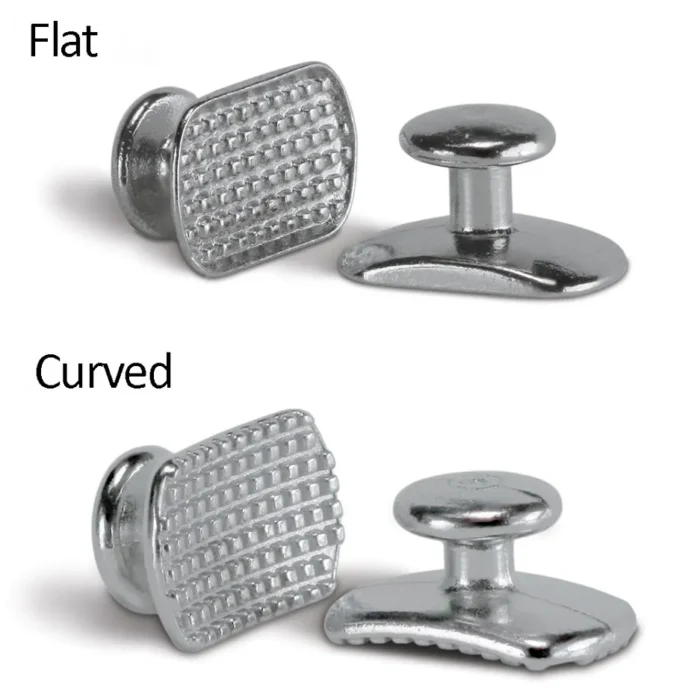

- Small rectangular shape

- Retains elastics from any angle

- Securely bonds on lingual or labial surfaces

- Rounded low profile design

- Made of high quality medical stainless steel

- Smooth finish for excellent patient comfort

Ortho Direct Lingual Buttons – Flat (Pack of 10)

Ortho Direct Lingual Buttons – Curved (Pack of 10)

Ortho Direct Lingual Buttons – Flat (Pack of 25)

Ortho Direct Lingual Buttons – Curved (Pack of 25)